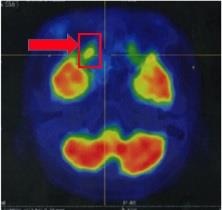

![]() ![]() ![]() |

| Sau 24 chu kỳ, khối u lympo của chị N.A đã tan. |

Các bác sĩ đã quyết định điều trị khối u của chị N.A bằng thuốc ức chế tụ điểm miễn dịch. Chỉ sau vài chu kỳ điều trị, khối u tan hoàn toàn, người bệnh hết đau, dễ chịu hơn mà không có tác dụng phụ nào.

Chị N.A là một trong số ít trường hợp u lympho tế bào T/NK ngoài hạch type mũi trên cả nước điều trị đáp ứng hoàn toàn. Sau 2 năm, với 35 chu kỳ điều trị dùng thuốc miễn dịch và được theo dõi sát sao, hiện chị N.A không có dấu hiệu tái phát - di căn. Trong tương lai, bệnh nhân tiếp tục được điều trị duy trì bằng thuốc miễn dịch này để đảm bảo hiệu quả chữa bệnh.